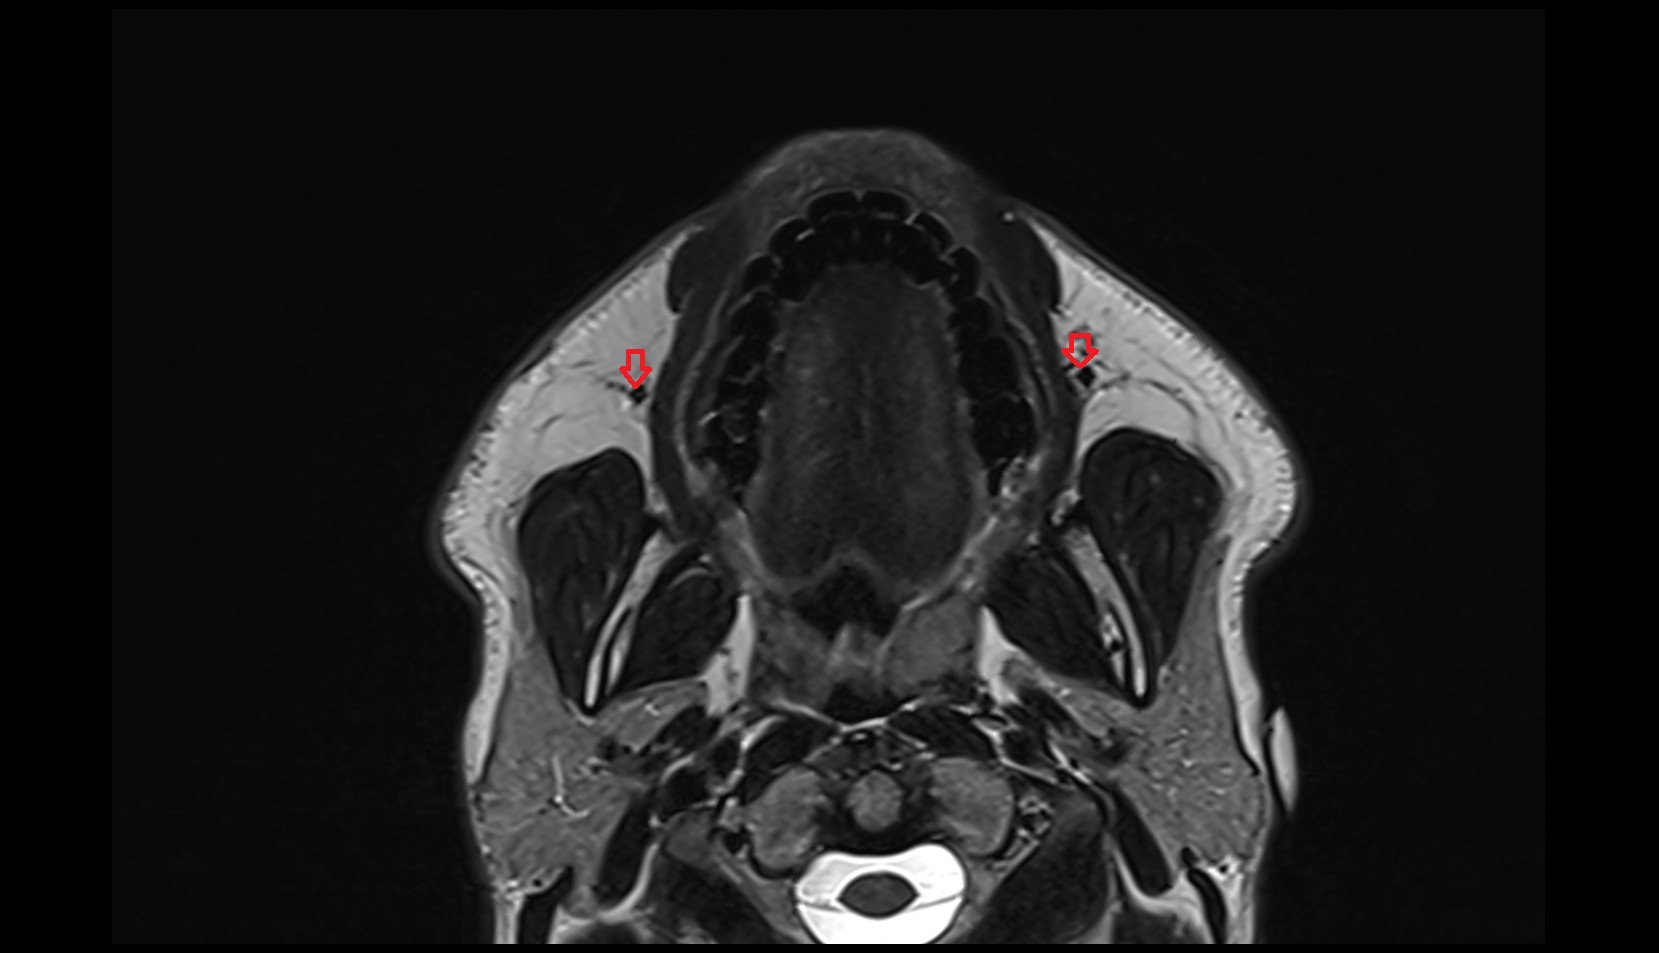

- Temporomandibular joint

- Mandibular condyle

- Mandibular fossa